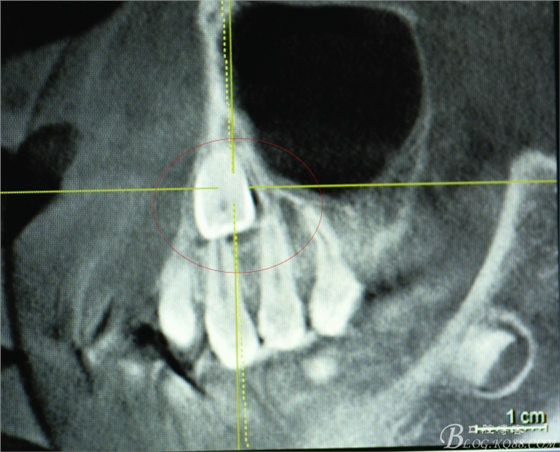

圖3.矢狀面檢查:23的唇面接近唇側(cè)骨壁、從而提示切口應(yīng)做在唇側(cè)。